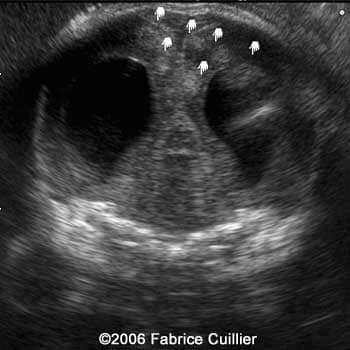

An ultrasound examination was performed in our unit at 30 weeks to evaluate the fetal anatomy. An abdominal scan demonstrated a bilateral hydrocephaly associated with echogenic signs on the brain suggestive of calcifications.

Serial coronal ultrasound view at 30 weeks showing bilateral ventriculomegaly

1